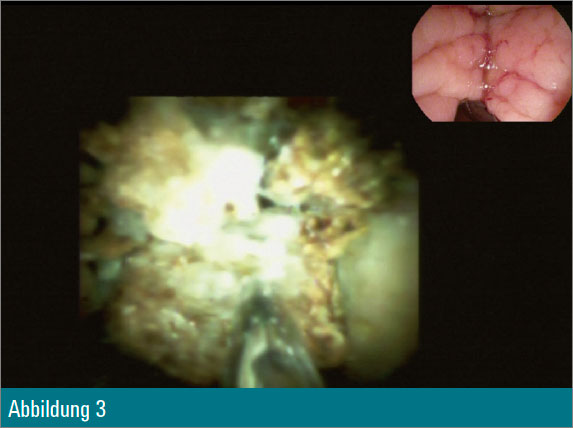

Eine 55-jährige Patientin wurde wegen eines Tonnenkonkrements im Ductus choledochus zur ERCP vorstellig (Abbildung 1). Nach Papillotomie erfolgte zusätzlich eine Ballondilatation der Papille auf 12 mm. Anschließend wurde mit dem Cholangioskop in den Ductus choledochus eingegangen (Abbildung 2) und eine elektrohydraulische Zertrümmerung des Konkrements unternommen (Abbildung 3).